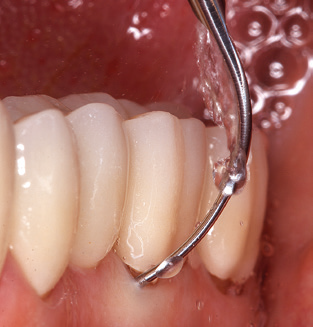

Good illumination of the working field facilitates the process considerably. The system used by the authors achieves this thanks to a 5x LED ring integrated in the handpiece. Naturally, a range of working tips for different indications is also offered. A straight, universally employable tip is the basic instrument required for machine cleaning of natural teeth (Fig. 5a and b). Curved tips, which allow access to exposed furcations, are also available for hard-to-reach areas in the posterior region (Fig. 6).

Following machine cleaning of the tooth and implant surfaces, the surfaces of the natural teeth are cleaned manually using standard hand instruments. When performing manual cleaning, particular attention must be given to maintaining the correct angle of application, appropriate sharpness, good support and working with the curette from apical to coronal. Either titanium or carbon curettes should be used for post-cleaning of the implant structures (Fig. 8). In addition to the use of ultrasonic devices, power jet devices can also be used in conservative dentistry. However, it must be taken into consideration that these procedures are not suitable for removing hard deposits and thus they cannot replace the use of hand instruments and ultrasonic instruments completely. In all cases, cleaning is followed by mechanical polishing of the accessible tooth and implant surfaces with polishing cups and polishing compounds (Fig. 9).